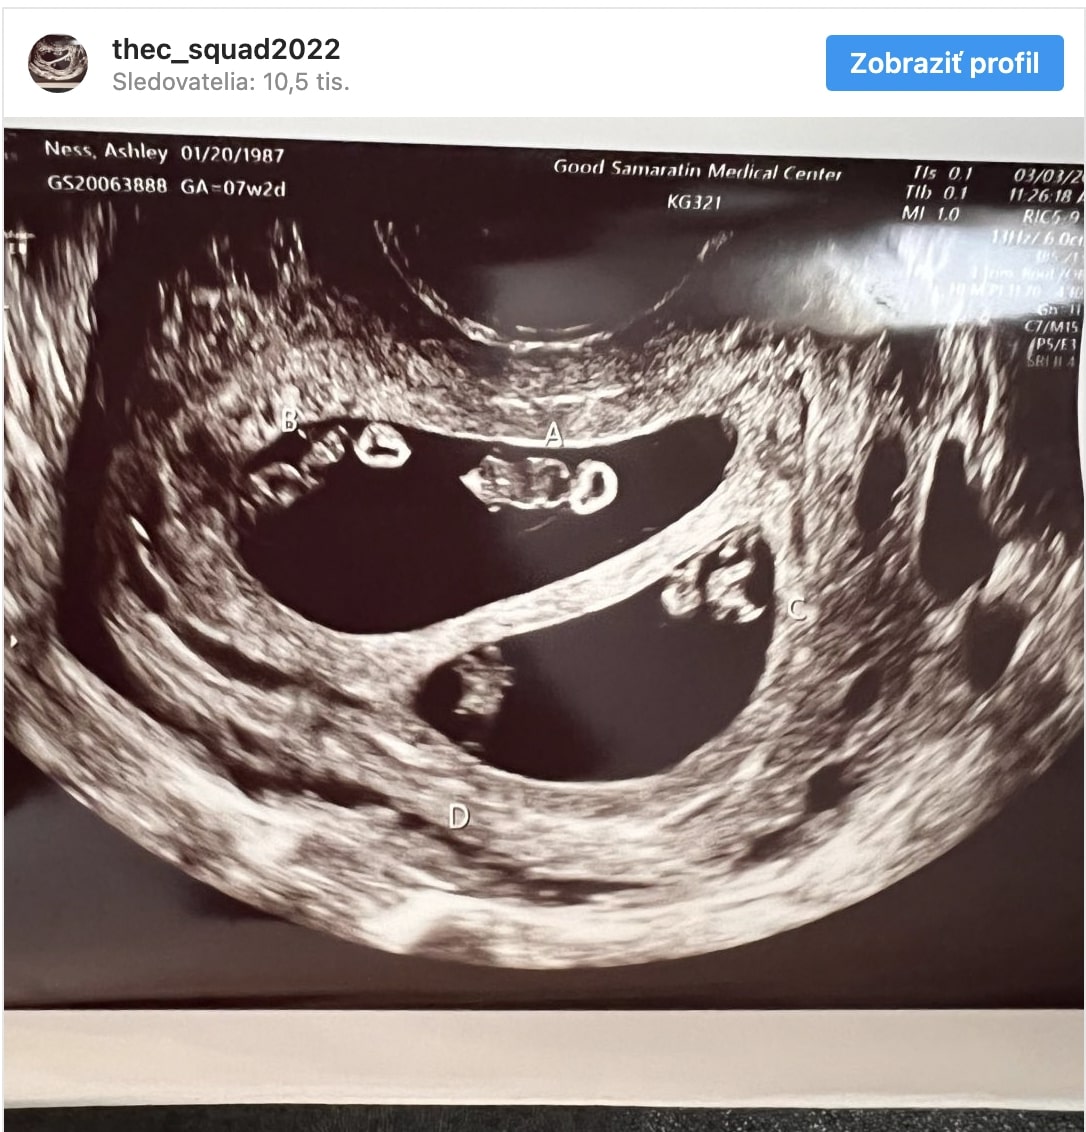

A People magazinnak nyilatkozó orvos elmondta, hogy annak az esélye, amilyen terhességet Ashley hord, 1 a 10 millióhoz. Egy rutinszerű ultrahangvizsgálat során kiderült, hogy a nő nem egy vagy két gyermeket hord a szíve alatt, hanem négyestr, hanem négyet – két pár egypetéjű ikret.